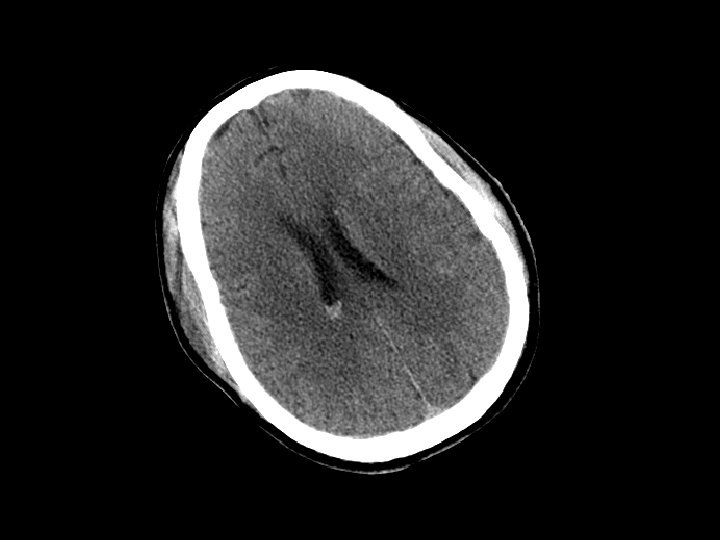

Tổn thương sợi trục lan tỏa • Lực xé và xoay làm gián đoạn hệ thống sợi trục • Cơ chế: chấn thương do tăng tốc và giảm tốc đột ngột • Chẩn đoán hình ảnh – Không rõ qua CT – MRI thể hiện rõ mức độ tổn thương • Không có biện pháp điều trị đặc hiệu • Có thể gây các tổn thương thần kinh trên bệnh nhân có CT bình thường nhưng tổn thương nặng